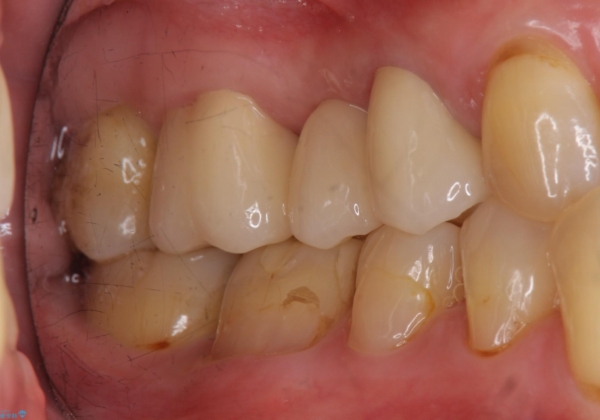

- 他院でブリッジの仮歯を入れたが、外れやすいため転院を希望された患者様です。

支台歯の形が角度が大きくついた形に形成してあり、外れやすい形になっていたため修正してから歯型をとりました。

- 36.3万円(ジルコニアクラウン10万円x3本)費用は治療当時の料金となります